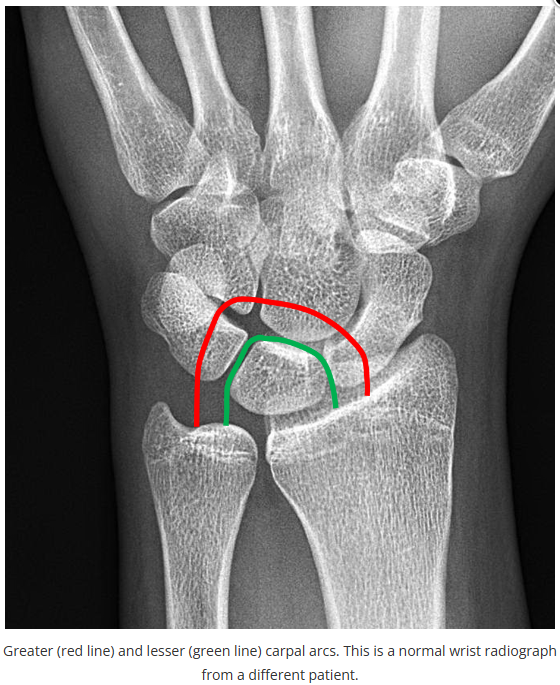

今天是腕部与手的X线片。所有X线片都

带有标注和说明

,可以选择长按图片,

自动翻译相关说明